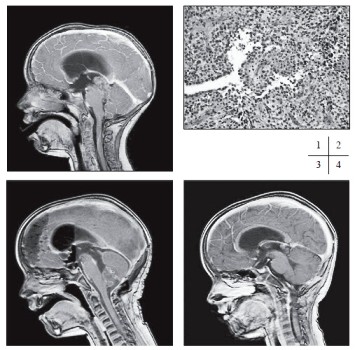

Pětiletá dívenka s negativní rodinou anamnézou se dostavila s příznaky syndromu intrakraniální hypertenze. Vyšetření MR prokázalo tumor pineální oblasti s propagací do III. a IV. mozkové komory velikosti 27 x 24 x 44 mm. Tumor byl v T1 zobrazení nehomogenní, obsahoval úseky cystické a solidní (obr. 1). Endoskopicky byla provedena ventrikulostomie s biopsií tumoru. V mikroskopickém obraze dominovalo papilární uspořádání nádoru s jemným fibrovaskulárním stromatem krytým nádorovými buňkami ve více řadách (obr. 2). Tumor byl nejprve klasifikován jako papilom choroidálního plexu, posléze přehodnocen na papilární tumor pineálního regionu G2-3.

Poté byla realizována ve dvou dobách kompletní resekce tumoru otevřenou cestou, časná MR nepopsala makroskopické residuum (obr. 3). Po intervalu čtrnácti měsíců došlo k lokální recidivě v dorsální části třetí mozkové komory o velikosti 13x10 mm (obr. 4). Recidiva byla ošetřena stereotaktickou radioterapií lineárním urychlovačem o energii 6 MV dávkou 48 Gy (16x3 Gy) s následnou postupnou regresí ložiska s následnou postupnou regresí ložiska.